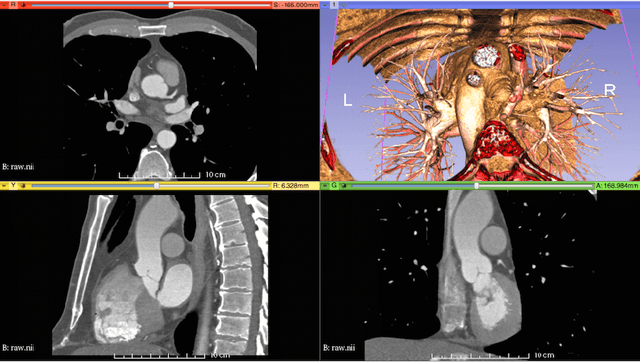

Abstract:Each year, approximately 300,000 heart valve repair or replacement procedures are performed worldwide, including approximately 70,000 aortic valve replacement surgeries in the United States alone. This paper describes progress in constructing anatomically and physiologically realistic immersed boundary (IB) models of the dynamics of the aortic root and ascending aorta. This work builds on earlier IB models of fluid-structure interaction (FSI) in the aortic root, which previously achieved realistic hemodynamics over multiple cardiac cycles, but which also were limited to simplified aortic geometries and idealized descriptions of the biomechanics of the aortic valve cusps. By contrast, the model described herein uses an anatomical geometry reconstructed from patient-specific computed tomography angiography (CTA) data, and employs a description of the elasticity of the aortic valve leaflets based on a fiber-reinforced constitutive model fit to experimental tensile test data. Numerical tests show that the model is able to resolve the leaflet biomechanics in diastole and early systole at practical grid spacings. The model is also used to examine differences in the mechanics and fluid dynamics yielded by fresh valve leaflets and glutaraldehyde-fixed leaflets similar to those used in bioprosthetic heart valves. Although there are large differences in the leaflet deformations during diastole, the differences in the open configurations of the valve models are relatively small, and nearly identical hemodynamics are obtained in all cases considered.